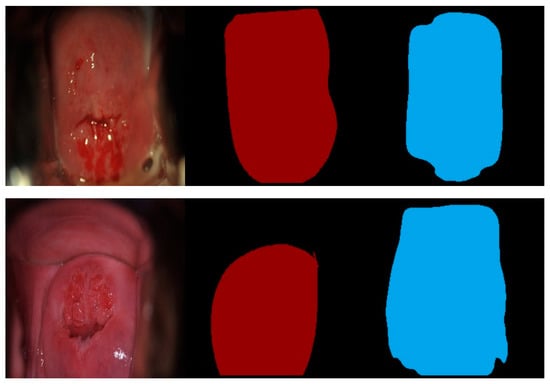

5.6. Error Cases